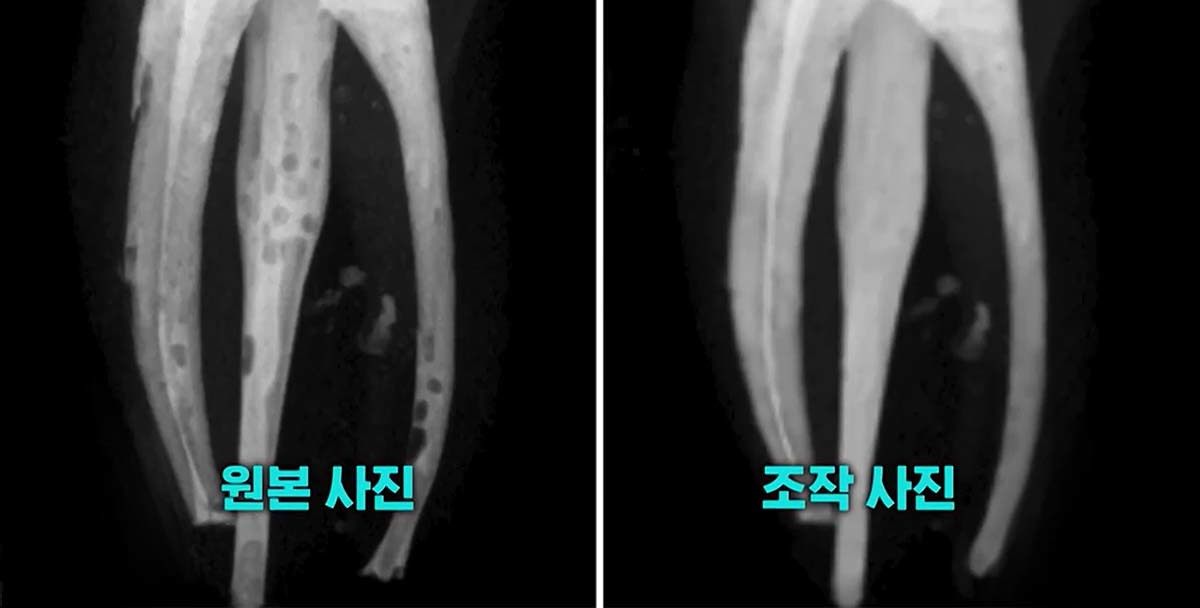

학생들이 제대로 치료하지 못한 치아의 엑스레이 사진을 포토샵 프로그램으로 조작해 마치 완벽하게 치료한 것처럼 제출했다.

원본 엑스레이 사진에는 신경치료 과정에서 충전재를 꼼꼼히 채워 넣지 않아 기포가 들어찬 모습이 여러 군데 보였다. 그러나 학생들이 교수진에 최종 제출한 사진은 기포 하나 없이 깨끗하게 치료된 모습이었다.